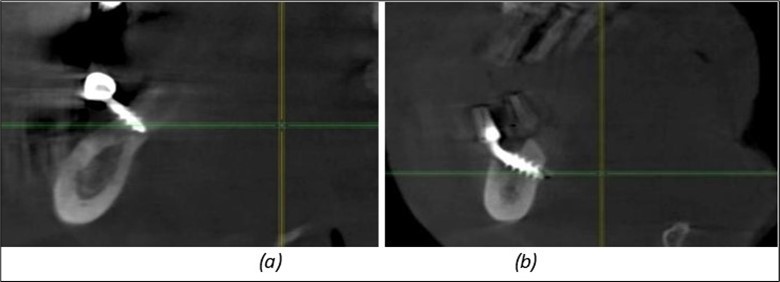

A total of 11 implants is placed in the maxilla, including compressive TPG implants with a polished surface in the maxillary-sphenoid fusion area (Figure 3, Figure 9). Similarly, in the anterior region, final fixation is achieved in the nasal cortex, and BCS corticobasal implants are added in areas with massive bone loss in the frontal region (Figure 3, Figure 8, Figure 11). Additionally, in the palatal sinus cortical area, with the aim of avoiding the addition and sinus lift zone where the second cortical bone no longer exists, 3 implants are placed, 2 in quadrant 1 and 1 in quadrant 2 (Figure 3, Figure 8). Through the Caldwell-Luc sinus lift procedure, the sinus cortical bone is displaced to allow the placement of the graft material and elevation of the sinus membrane. This sinus cortical is no longer recreated at the junction of the graft material and mucosa-sinus membrane, making it impossible to place a corticobasal implant, which relies on the second cortical bone. In the distal mandibular area, after the removal of two stage implants due to massive destruction in quadrant 3, implant placement distal to the mylohyoid line is not possible, as in quadrant 4 (Figure 10). A re-intervention occurs after 5 months to stabilize the area (Figure 12, Figure 14). Also, at the moment of fixation, the tip of one implant fractures, and the decision is made to leave it in place due to regional bone destruction, in order to avoid enlarging the bone defect.

Considerations related to connective tissue grafting in post-extraction and post-implant defects – it is a technique that can be performed either by harvesting connective tissue from the tuberosity area, the palate, or the marginal palatal area, if the quantity is sufficient 11. It is done simultaneously with the rest of the bone regularization procedure; in this case, removal of the palatal gingival area was necessary anyway for easier cleaning and access to the frontal implants. On this occasion, after de-epithelialization, the tissue is used to restore the shape of the frontal gingival area after implant insertion (Figure 4, Figure 5).

Figure 12.Implants fixed distally in quadrant 4 with fixation at the level of the mylohyoid line: (a) The most distal implant fixed in unaffected bone from the previous restoration; (b) The implant fixed in the area where the two stage implant was removed.